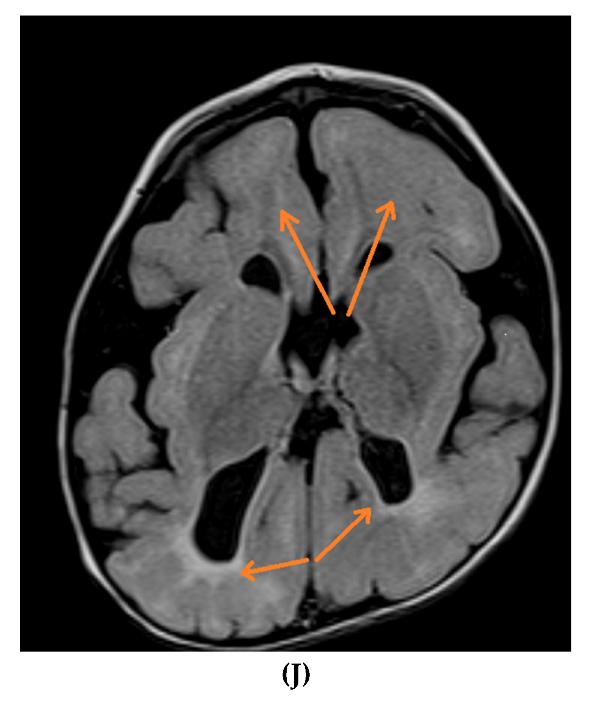

Figure 2.

Brain MRIs showing the following (A): signs of hypoxia (T2 axial) with diffuse periventricular leukomalacia, enlarged ventricles and global atrophy (arrows); (B): delayed myelination in a 2-year-old child with diffuse hyperintense white matter compared to gray matter and brainstem (T2 axial); (C): dysgenesis of corpus callosum affecting its rostrum, genu, trunk and splenium (T1 sagittal) (arrows); (D): diffuse brain atrophy with enlarged ventricles (T1 axial); (E): severe ventricular dilatation (T2 axial) in a child with congenital muscular dystrophy; (F): intraventricular hemorrhage III (arrows) and hydrocephalus (T1 axial); (G): periventricular leukomalacia (T2 axial) (arrows); (H): non-specific white matter changes right precentral (T2 coronal) (arrows); (I): right frontal cortical tuber in a child diagnosed with tuberous sclerosis (T2 axial) (arrows); (J): PVL and frontal pachygyria (T2 axial) (arrows).